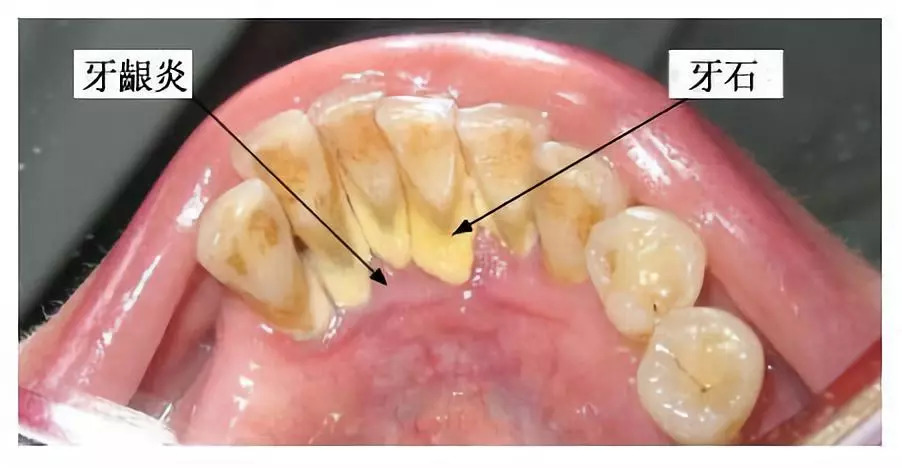

另外就是牙结石,牙结石起初是乳白色,但慢慢会随着牙龈出血、烟酒或喝咖啡等习惯变成黑褐色。

牙结石虽小但危害极大,如果不及时清除则会破坏牙周,刚开始时会牙龈红肿出血,但时间一长牙槽骨会“发炎”,然后造成“骨丧失”,就像大树和树根的关系。

牙石的堆积、牙龈的炎症会让牙龈肿胀填塞,洗牙后去除了牙石,牙龈肿胀逐渐消退,所以会感觉牙缝好像变大了。

但其实这才是牙齿的庐山真面目,绝非洗牙所造成的。

事实上,如果不洗牙,牙结石造成牙周炎会使牙齿松动,牙缝反而会不断变大。